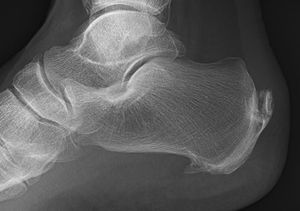

Cal... fracture! ?

Heel fracture?

Calcaneal spur

Bone spur on the heel.

Calcaneal spur - patient compliants recurrent heel pain with symptoms of Arthiritis

It’s calcaneal fracture guys, thanks for your attention:)☺️